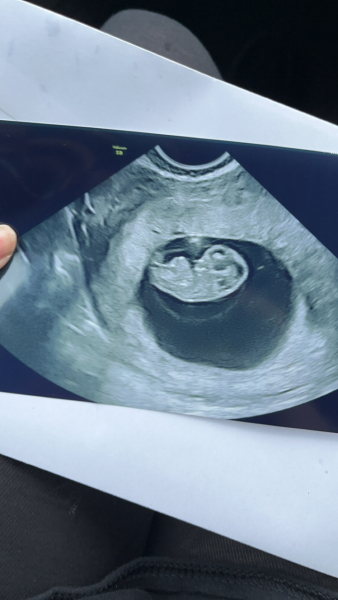

Here is my 8+2 scan from Sunday :)

Jadelr · 01/03/2024 17:58

Hi just thought I would update this post for anyone that is looking for reassurance etc. I had my scan today and i got to see a healthy baby wriggling about 🙈 I'm in utter shock. I'm measuring 9weeks 1 day even though I'm only 8weeks2 days. Got to see and hear babies heartbeat 🥰🖤

Private Scan at 8 Weeks

@SH998 Thankyou lovely! It's such a surreal feeling, seeing the baby wriggle around and hearing its heart beat. I'm in awe and I'm so so pleased 🥰 xx